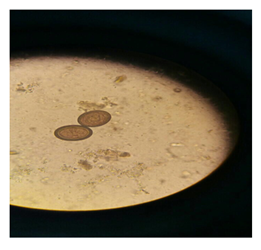

Figure 2 Taenia Ova.

Taenia (tapeworm)

Tapeworms from eating raw meat and cooked cow or pig to a human patient are infectious. Kind of cattle passes long disease that causes pain, weakness and severe anemia patients.4